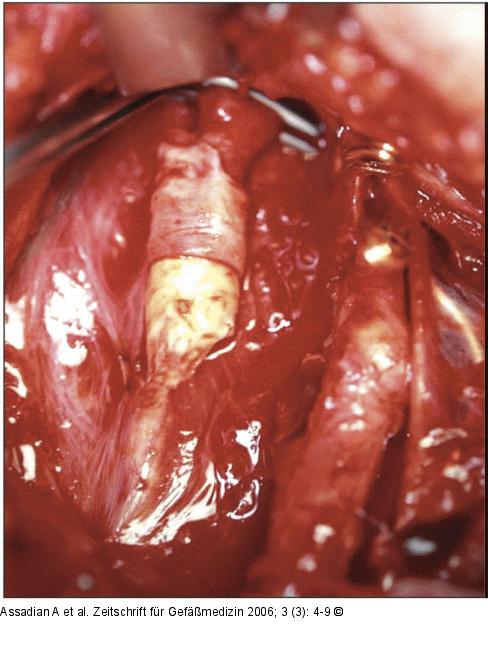

Abbildung 2c: Arteria carotis communis Durchführen der Eversionsendarterektomie der ACI. Dabei wird das pathologische Substrat der Stenose entfernt. |

Durchführen der Eversionsendarterektomie der ACI. Dabei wird das pathologische Substrat der Stenose entfernt. |